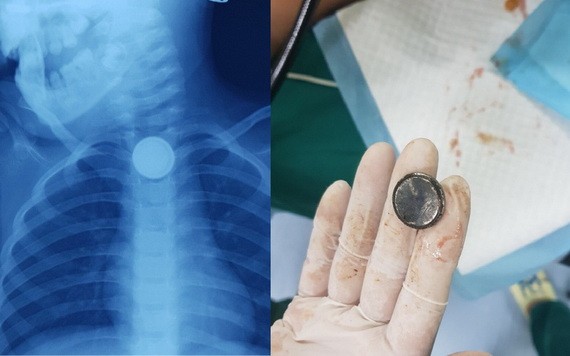

左圖:X光片上顯示,食道內有一棵類似紐扣型電池的異物卡住;右圖:經軟管內窺鏡手術從女童食道取出一棵紐扣型電池。(圖源:院方提供)

此前,上述女童嬉戲時誤吞一顆紐扣型電池後被卡在食管內。事發4小時後,該女童才獲家長送往醫院檢查並取出異物。在醫院,經診病與內窺鏡觀察,醫生發現紐扣型電池導致食管表面灼傷與發黑。該女童獲指定施內窺鏡手術取出異物,醫生從食管取出一顆圓形紐扣型電池。消化內窺鏡科主任阮清平醫生表示,該科經常收治上述類似病童誤吞異物病例。異物有的是鐵珠、骨刺、紐扣、耳環與紐扣型電池等。